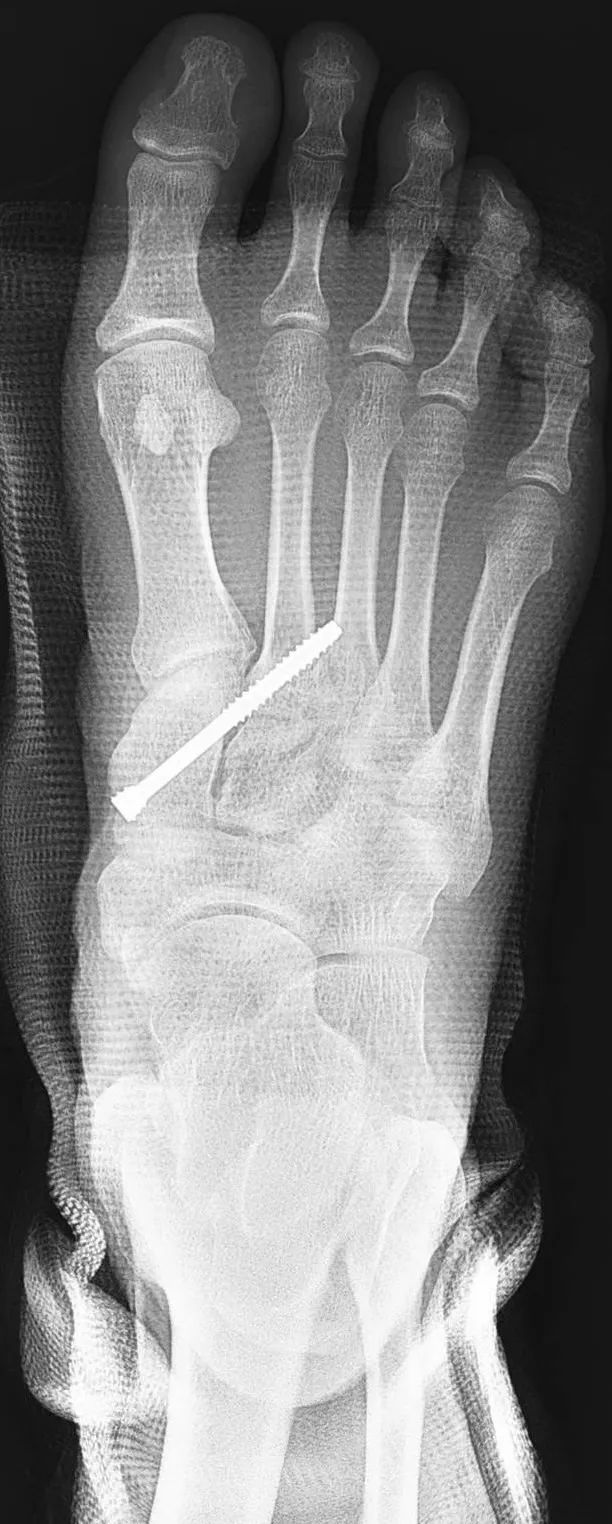

患者接受微創鋼釘固定手術治療後的x光照。大里仁愛醫院提供